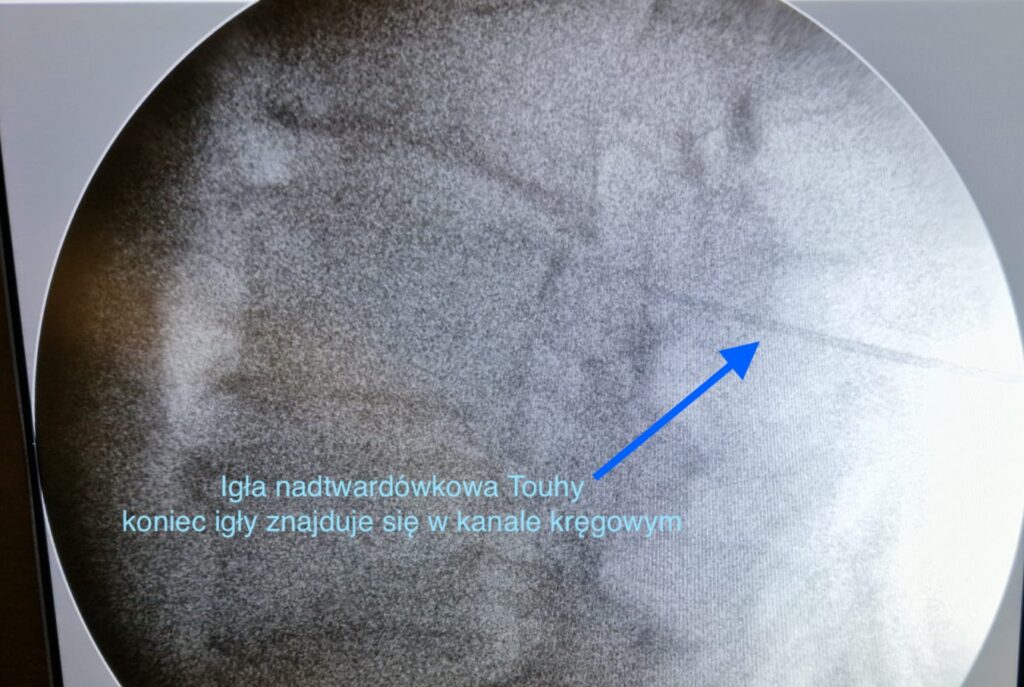

Więcej rzetelnych informacji na temat iniekcji nadtwardówkowych prezentujemy tutaj.